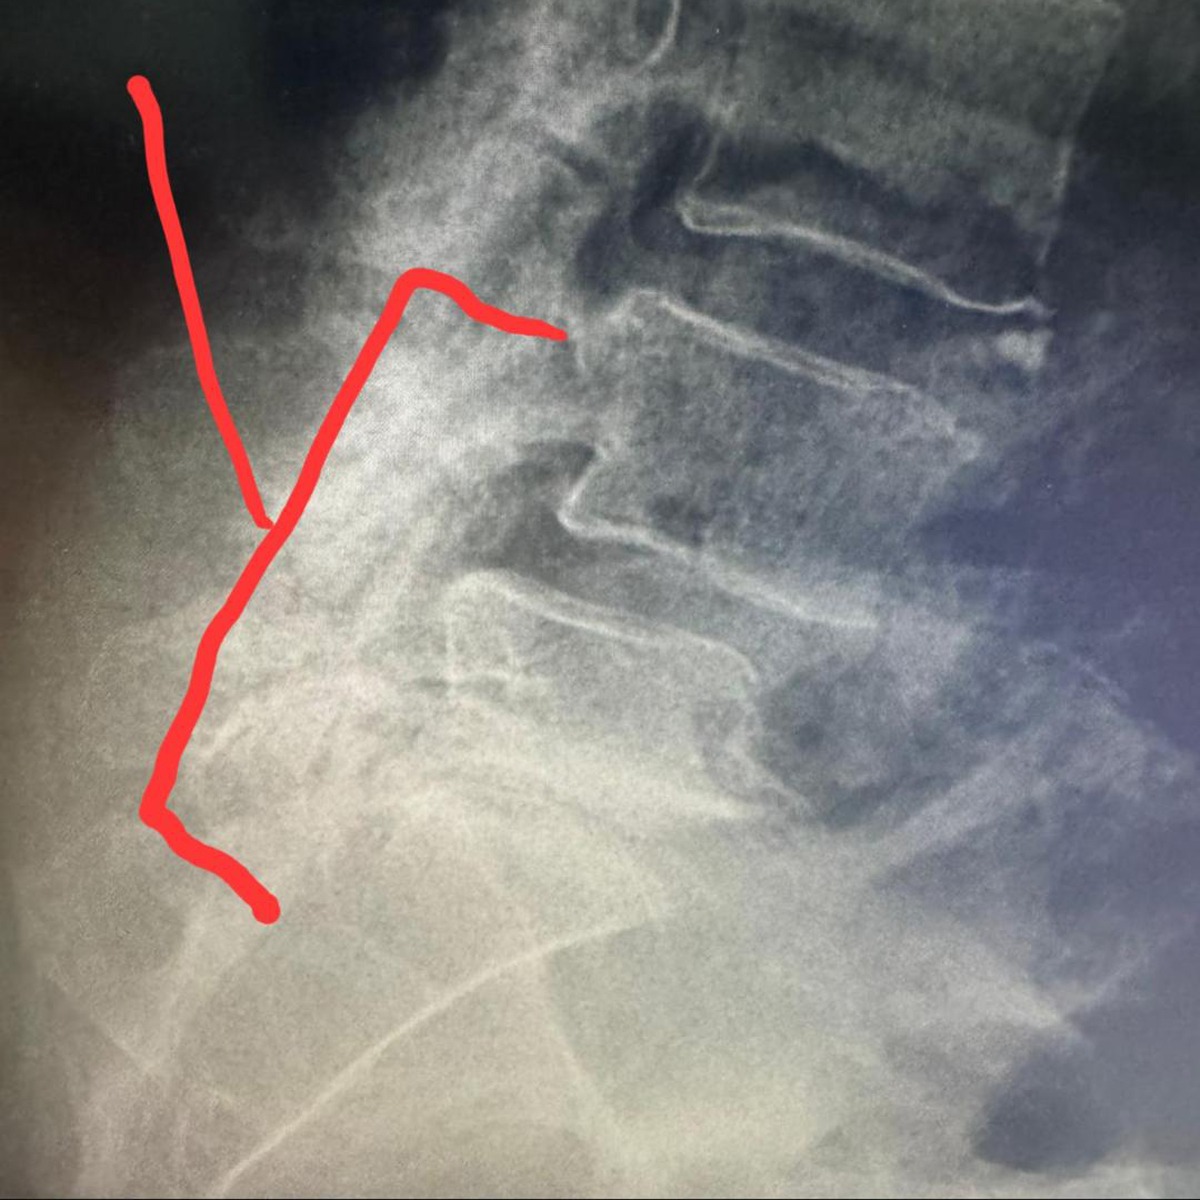

Recently, she suffered a serious fall that fractured her coccyx and caused damage to her lower spinal vertebrae. She was hospitalized in extreme pain, and is now facing major surgery and extensive physical therapy to heal and regain full mobility. Unfortunately, a clerical error some time ago caused the cancellation of her medical insurance, leaving her with no coverage for this urgent medical care.